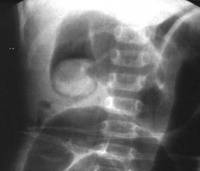

小肠梗阻

X线站立位时见小肠“阶梯样” 液平。平卧位时见积气肠管进入盆腔

小肠梗阻X线